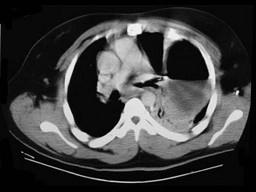

问题 35岁,男,因车祸入院,呼吸困难、发绀、上腹痛,请结合胸片和CT选择最可能的诊断 ( )

选项 A、膈麻痹 B、液气胸 C、胸腔积液 D、膈膨升 E、膈疝

答案 E